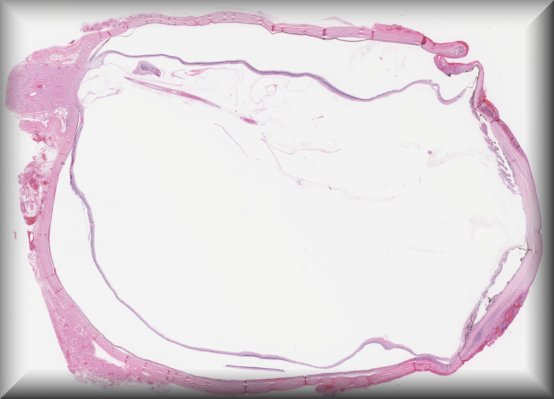

Stefan J. Lang (Freiburg): Graft failure after DMEK surgery |

![]() |